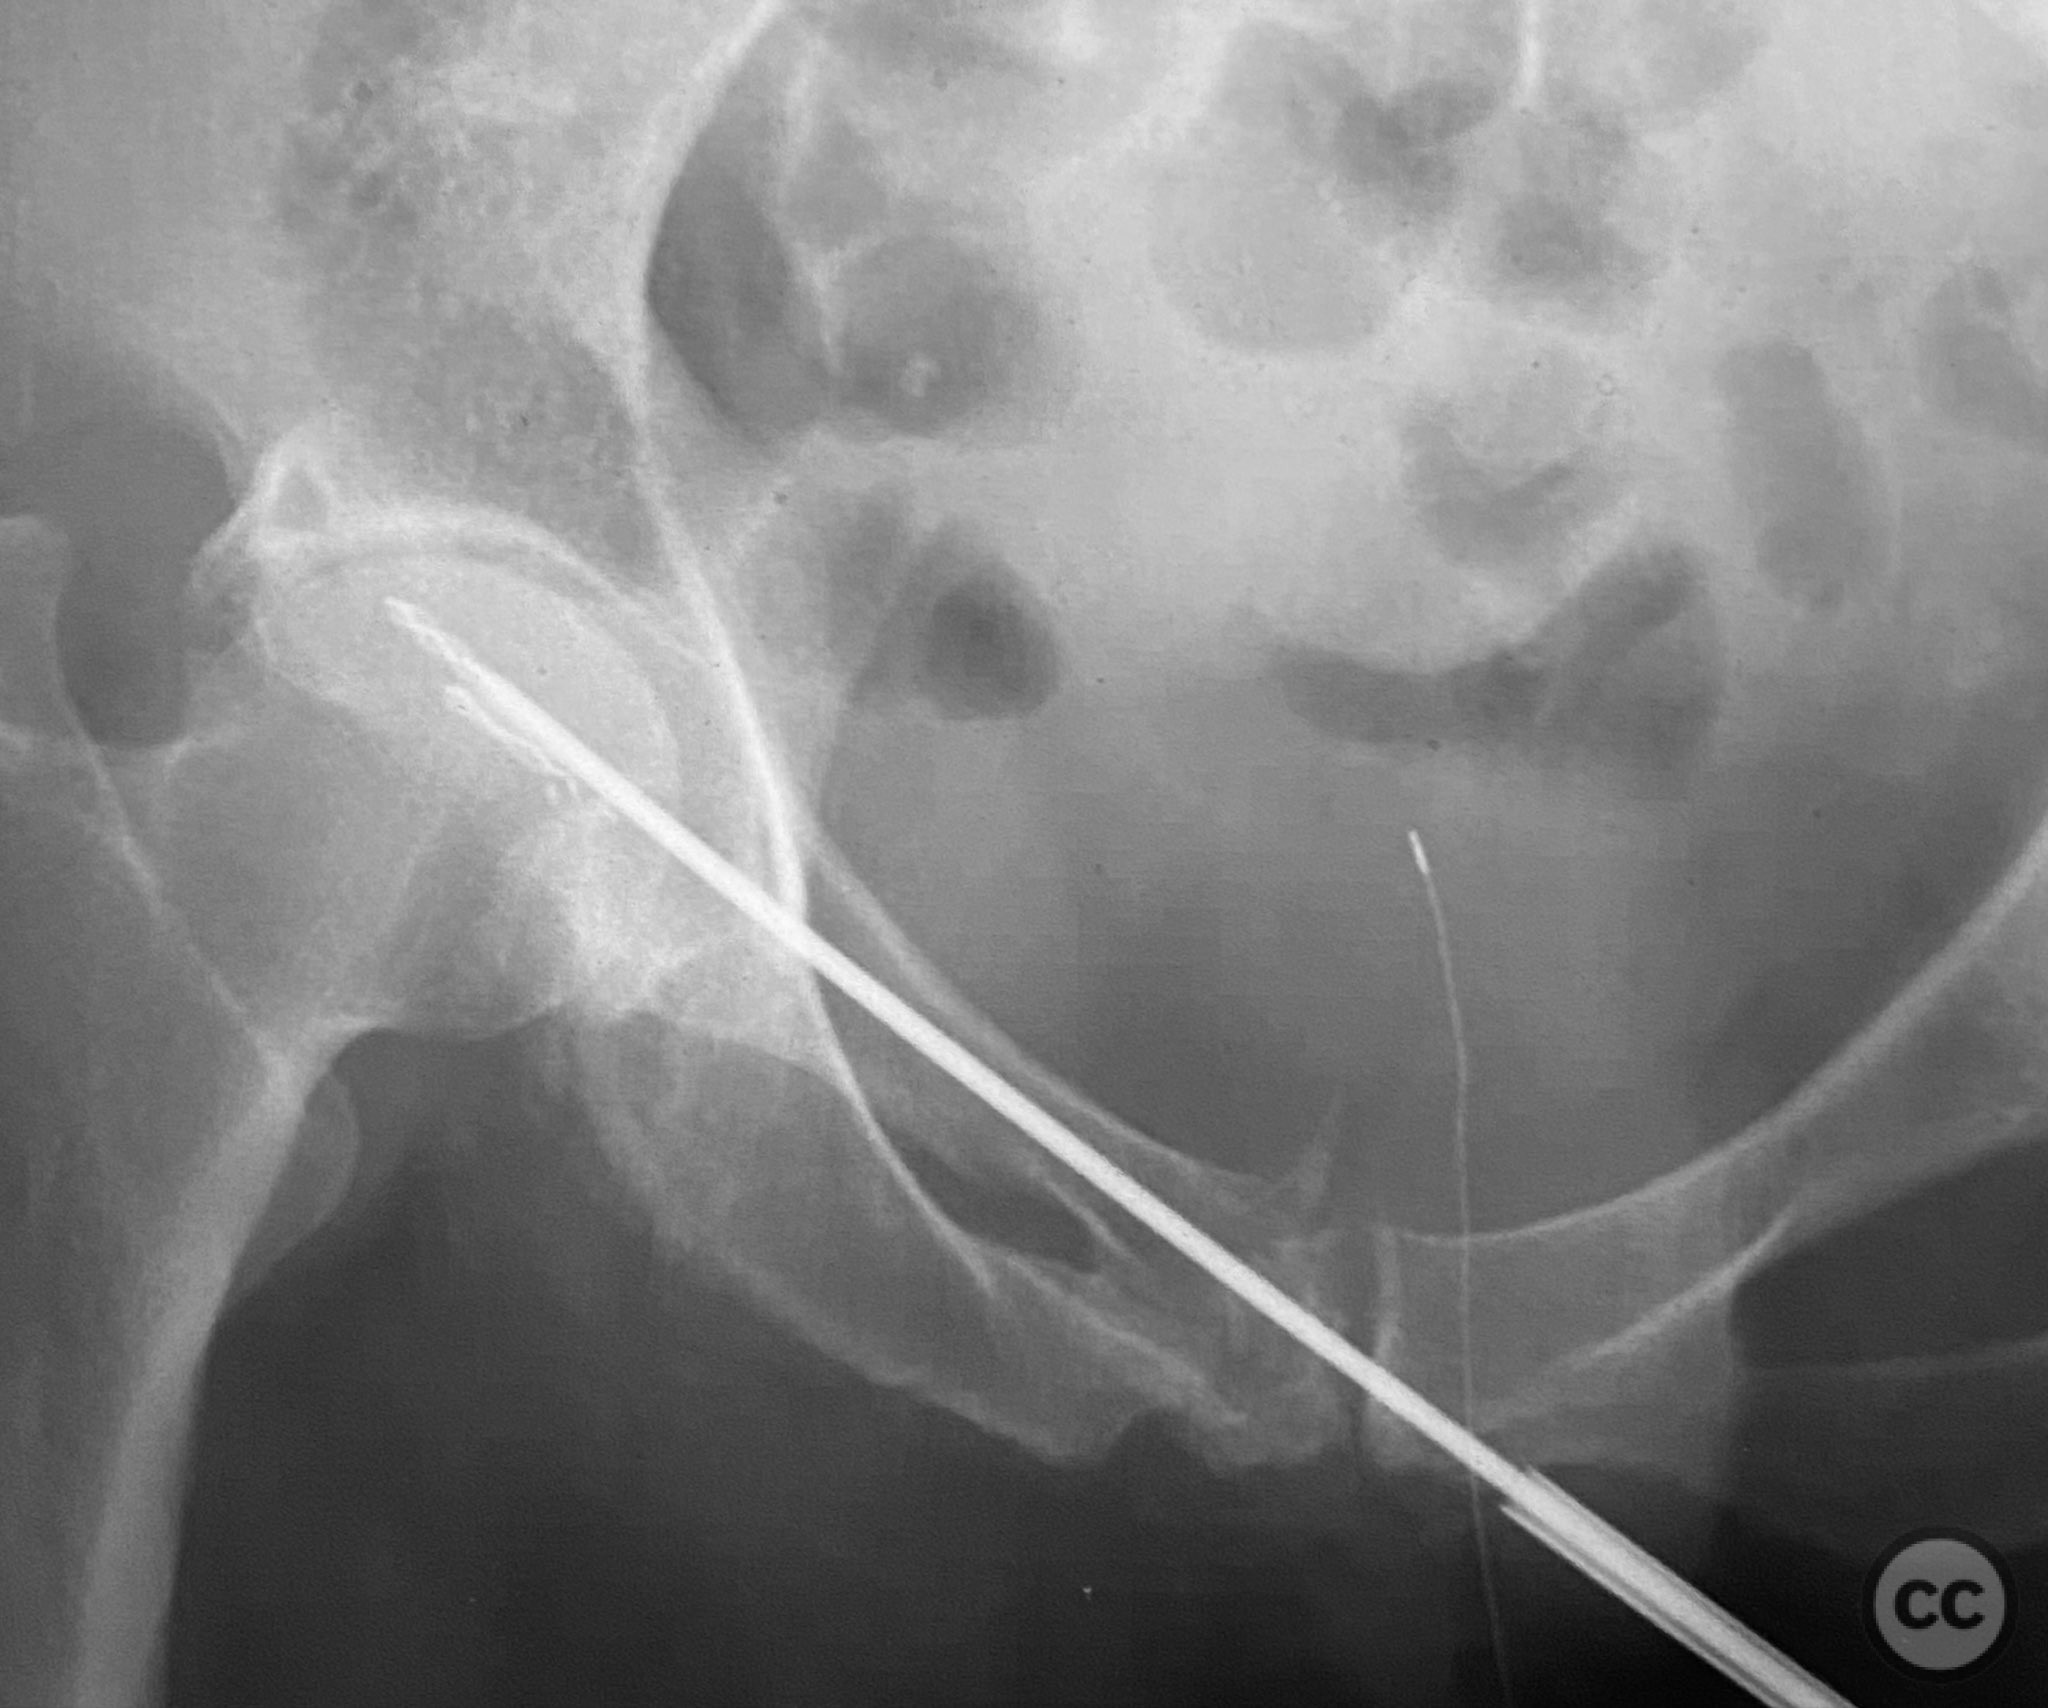

Clinical and radiological findings:  Adult patient presenting with severe pelvic pain, unable to sit or transfer to a chair. Clinical examination under anesthesia demonstrated pelvic instability with “rebound reduction” upon minimal iliac crest compression. Imaging revealed an unstable superior pubic ramus fracture with challenging anterior pelvic bone anatomy and dense cortical bone at the anterior acetabular wall.

Planning remarks:  Planned trans-symphyseal fixation of the superior pubic ramus fracture using a 4.5mm cortical screw, with preoperative intent to maximize implant purchase in stable bone regions. Surgical approach selected to facilitate direct access to the superior pubic ramus and symphysis pubis.

Intraoperatively, a 3.5mm drill was used through a protective sleeve to initiate the screw pathway across the superior pubic ramus. Due to poor bone quality, a 2.5mm drill was subsequently employed; however, resistance was encountered as the drill tip engaged the dense cortical apex of the anterior acetabular wall. The drill became lodged in this region. To avoid drill breakage, manual extraction using pliers was considered; however, the surgeon elected to carefully deflect and advance the drill manually, successfully completing the pathway. Screw length was measured directly from the embedded drill tip. A 4.5mm cortical screw was then inserted trans-symphyseally along the prepared medullary canal, achieving stabilization of the unstable ramus fracture. Postoperative CT confirmed appropriate screw trajectory and demonstrated the dense cortical bone at the anterior acetabular wall where the drill tip had engaged.